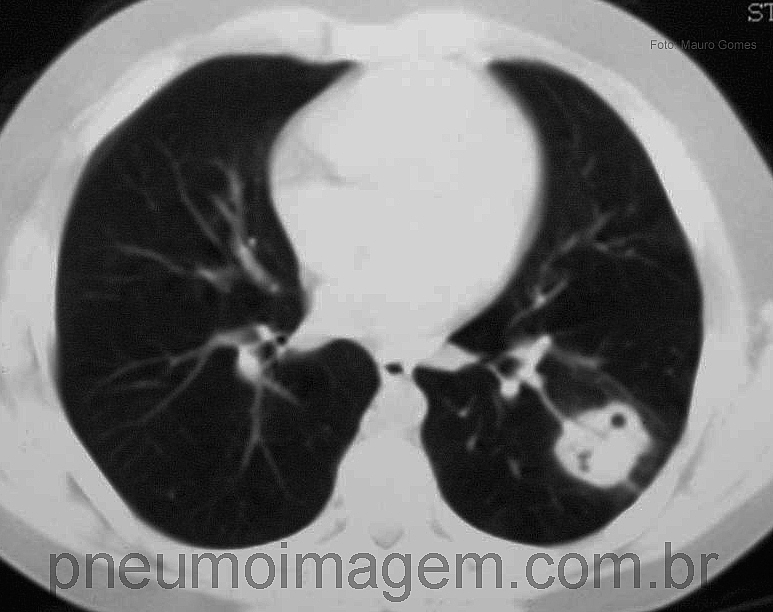

CASO CLÍNICO #38Menino adolescente de 12 anos de idade com opacidade nodular em lobo inferior esquerdo. Apresentava exposição a pombos no pátio do colégio em que estudava. Qual o diagnóstico mais provável? Deixe os seus comentários abaixo.

Teen boy of 12 years old with nodular opacity in the left lower lobe. Had exposure to pigeons in the schoolyard where he studies. What is the most likely diagnosis? Give your comments below.

Criptococose.